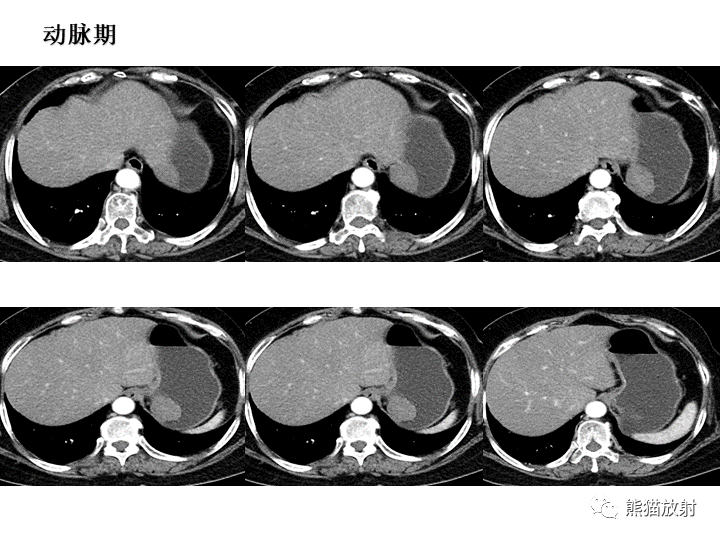

【病例】胃间质瘤VS神经鞘瘤-2